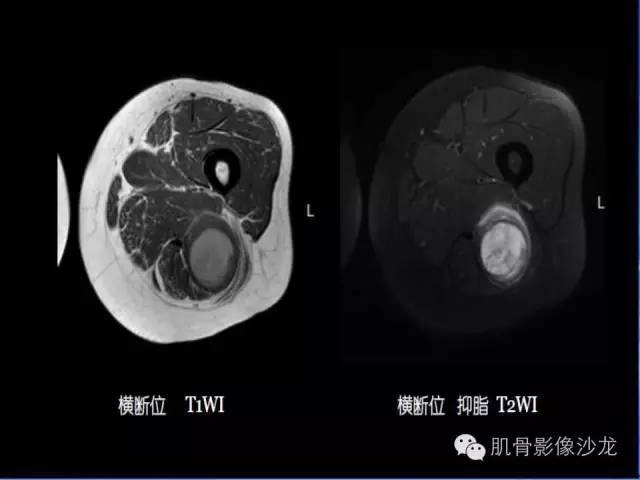

【病例】恶性外周神经鞘膜瘤1例MR影像表现